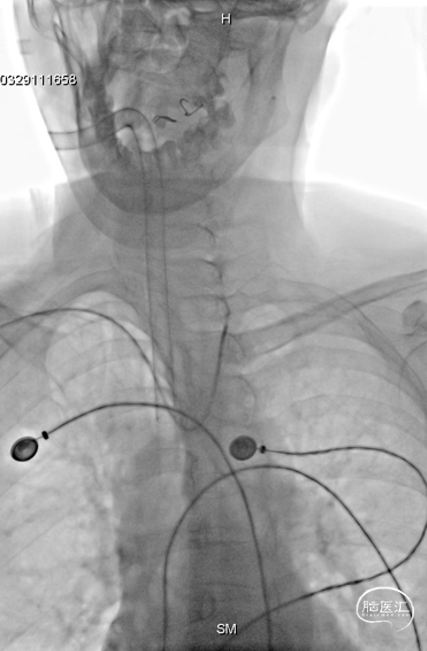

右侧桡动脉穿刺,穿刺成功后置入6F薄壁动脉鞘,随后使用TRUST技术置入Tethys®中间导引导管(内衬5F Simmon导管)输送至锁骨下动脉,弓上勾选至左侧颈总动脉后,Tethys®中间导引导管顺滑输送至左侧颈内动脉成功建立治疗通路,为后续致密栓塞及释放支架提供重要支撑.